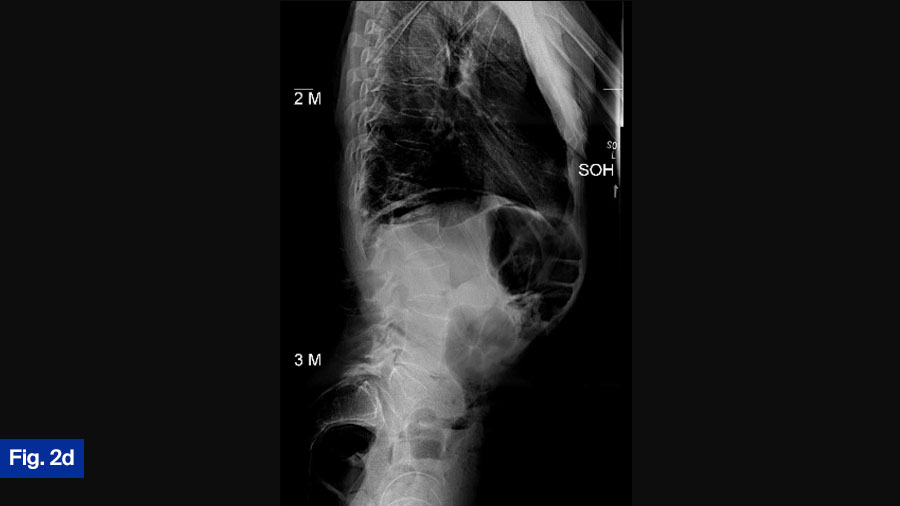

Actual treatment

Ultimately, the patient was treated with intravenous vancomycin for 8 weeks via PICC line—this included a 10-day inpatient stay prior to discharge. He was transitioned to oral antibiotics with Septra (sulfamethoxazole & trimethoprim) for 6 months. Standing films demonstrate adequate alignment (Figure 2D). Patient was doing well at the most recent follow-up and remained neurologically intact.